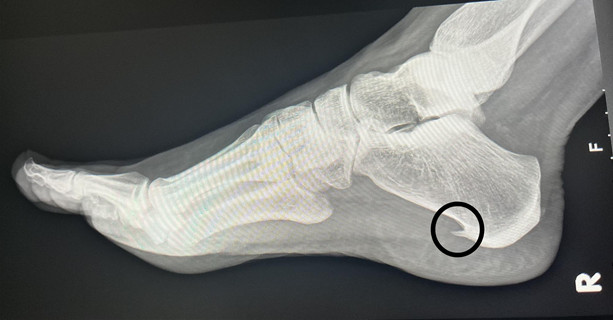

Petni trn predstavlja jedan od najčešćih i najneugodnijih problema stopala koji može značajno uticati na svakodnevni život. Ova bolest, koja se medicinski naziva plantarni fasciitis, karakterizirana je pojavom boli u području pete uzrokovane upalom plantarne fascije. Simptomi koji se javljaju kod ove tegobe često su toliko izraženi da obične aktivnosti, poput ustajanja iz kreveta ili hodanja, postaju pravi izazov. Bolovi se obično javljaju ujutro ili nakon dužeg sjedenja, a obično su praćeni osjećajem nelagode tokom dana. Iako fizički ne predstavlja ozbiljnu prijetnju zdravlju, njegov uticaj na kvalitet života je neosporan.